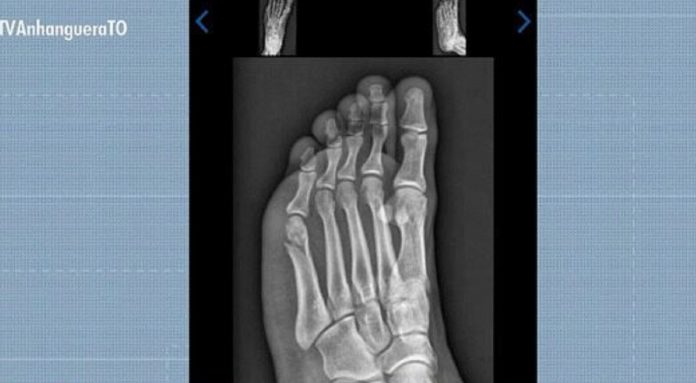

Gabriel Santos Rodrigues foi aprovado no TAF da PMTO mesmo com fratura no pé

Reprodução/TV Anhanguera